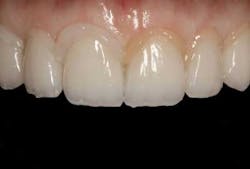

Fig. 17ConclusionBy incorporating the Tack & Wave technique into their clinical protocol, dentists can realize a convenient and effective way to remove excess cement from restoration margins and interproximal areas when placing all-ceramic veneer restorations. New resin cement systems now available make it easy to set resin in a “semi-gel” state, so clinicians can initially place veneers without them drifting and subsequently quickly and easily peel away the excess cement in more time-efficient and less technique-sensitive manner (See Figs. 18-23).

Fig. 18

Fig. 19

Fig. 20

Fig. 21

Fig. 22

Fig. 23Author bioDavid S. Hornbrook, DDS, FAACD, a gifted clinician and product researcher turned mentor, guides meeting participants to the realization that they, too, possess the ability to practice esthetic dentistry at the very highest level. He is one of dentistry’s most famous faces and one of the pioneers of live-patient, hands-on clinical education, as the founder and past director of Pac-live and the Hornbrook Group. He has been a guest faculty member of the postgraduate programs in cosmetic dentistry at Baylor, Tufts, SUNY at Buffalo, UMKC, and the UCLA Center of Cosmetic Dentistry. Dr. Hornbrook lectures internationally on all facets of esthetic and restorative dentistry and has published articles in all of the leading dental journals. A prolific researcher and materials enthusiast, he consults with numerous manufacturers on product development and refinement. Dr. Hornbrook’s warm and engaging style earns him the highest possible marks from participants and meeting sponsors.